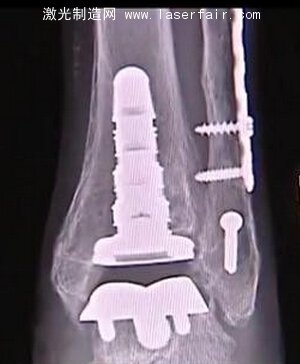

Brown醫生精通最新的技術,他決(jue) 定使用一個(ge) 相對較新的手術方法。他使用一截最先進的3D打印假肢“inbone”置換了Dube的整個(ge) 腳踝。

3D打印能夠根據Dube的個(ge) 人特征為(wei) 其量身定做特殊的腳踝,效果要比過去的一些傳(chuan) 統的踝關(guan) 節置換好得多。雖然Dube的腳踝不能100%地恢複到她跌倒以前的狀況,而且她再也不能穿高跟鞋,手術仍然是令人難以置信的成功。

在踝關(guan) 節置換中的3D打印部分可以保持大約10年,隻要Dube遵循醫生的囑咐,注意她的重量,並且穿減震的鞋子。